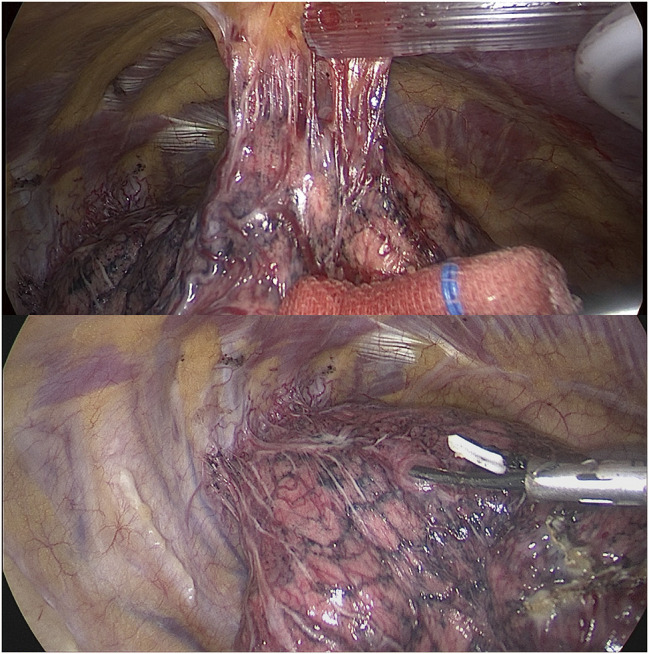

单侧肺动脉缺失(UAPA)是一种不常见的先天性畸形。在较罕见的情况中,UAPA 合并肺癌的病例此前已有 13 例报道;然而,关于手术方法和注意事项仍存在争议。在此,我们介绍了一例 56 岁女性患者的病例研究,她在一次常规体检中偶然被诊断为右肺下叶结节,随后在术前评估中发现右肺动脉缺失。患者接受了右肺下叶楔形切除术。术后病理证实为浸润性腺癌(pT1N0M0)。我们对有关这些患者的现有文献进行了叙述性回顾,并讨论了最佳手术治疗策略。

Unilateral absence of a pulmonary artery (UAPA) is an uncommon congenital anomaly. Among the rarer conditions, UAPA with lung cancer has been previously reported in 13 cases; however, there remains controversy regarding the surgical approach and precautions. Herein, we present a case study of a 56-year-old female patient who was incidentally diagnosed with a nodule in the right lower lobe of the lung during a routine physical examination and subsequently found to have an absent right pulmonary artery upon preoperative evaluation. A wedge resection of the right lower lobe was performed as treatment. Postoperative pathology confirmed invasive adenocarcinoma (pT1N0M0). We provide a narrative review of existing literature on these patients and discuss optimal surgical management strategies.